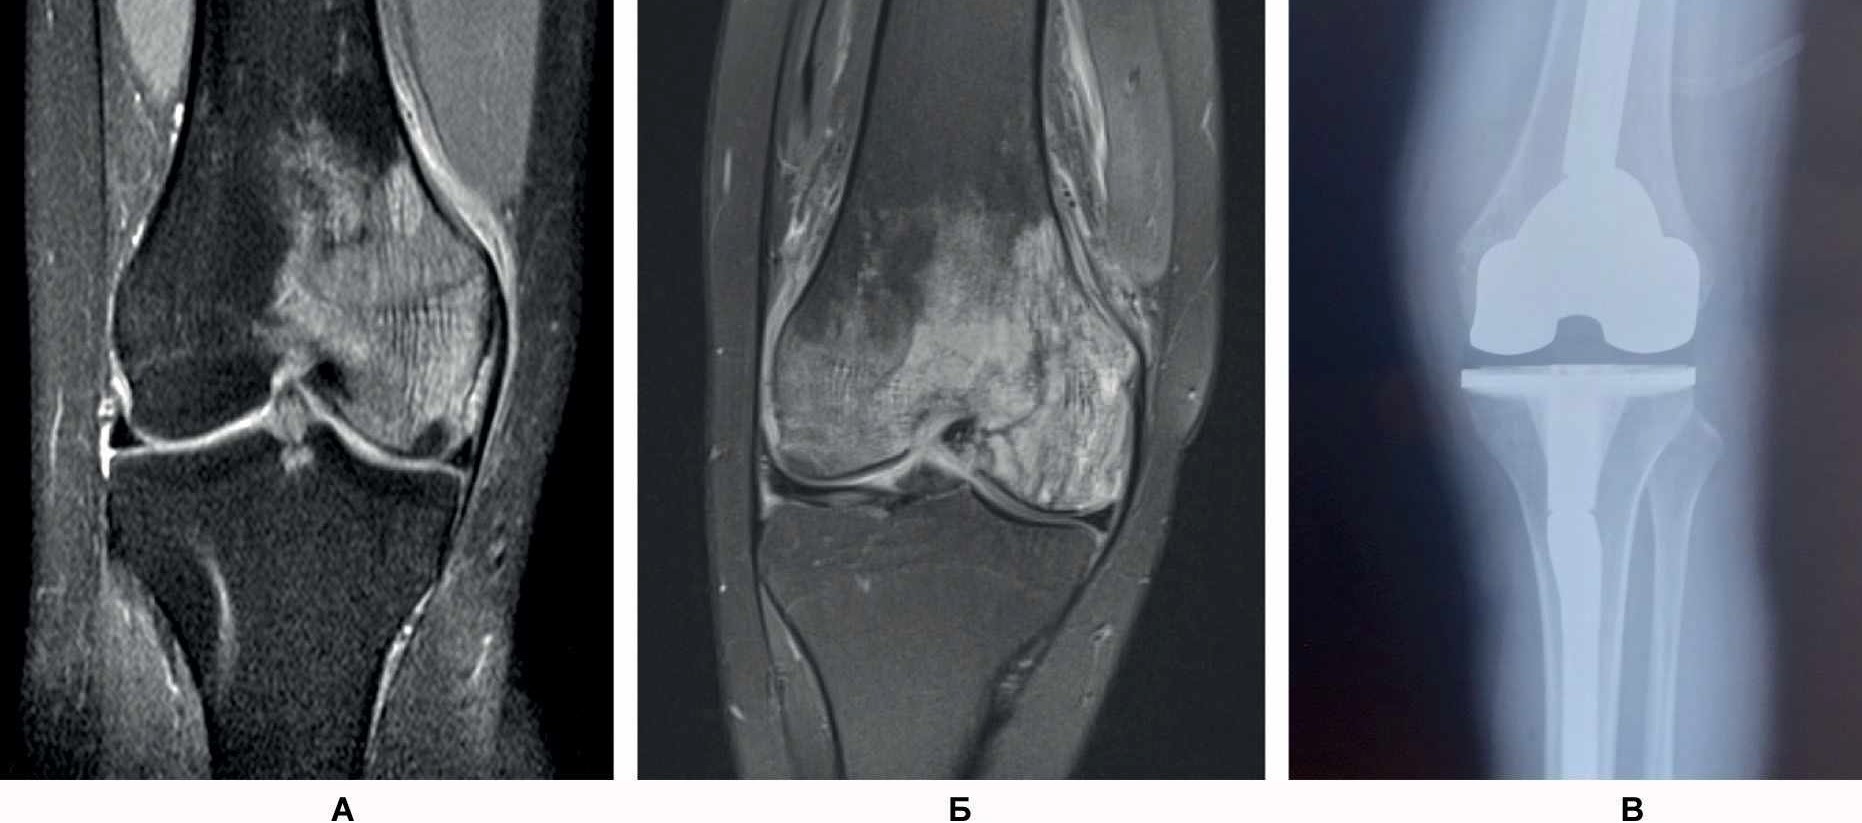

- Женщина А., 27 лет. При обращении жалобы на распирающую, пульсирующую боль в области медиального мыщелка левой бедренной кости и ночную боль (интенсивность – 7 баллов по визуально-аналоговой шкале боли, ВАШ) в левой ноге. Отмечается нарушение опороспособности на левую нижнюю конечность. Соматический и наследственный анамнез не отягощен. В мае 2021 г. перенесла острую респираторную вирусную инфекцию в легкой форме. 06.10.2021 г. выполнена спиральная компьютерная томография (СКТ) левого коленного сустава, обнаружен асептический некроз медиального мыщелка левой бедренной кости (рис. 1А). 25.11.2021 г. выполнены артроскопия левого коленного сустава, декомпрессия очага некроза. Назначено консервативное лечение. 16.01.2022 г. проведена контрольная МРТ – асептический некроз медиального мыщелка левой бедренной кости (см. рис. 1Б).

Рис. 1. СКТ левого коленного сустава у пациентки А. Диагноз: асептический некроз медиального мыщелка левой бедренной кости: 06.10.2021 г. (А), 25.11.2021 г. (Б), эндопротез левого коленного сустава (В).

На контрольном осмотре пациентка отмечает постоянную боль тянущего характера по медиальной поверхности левого коленного сустава, резкую боль (7 баллов по ВАШ) в области медиального мыщелка левой бедренной кости при попытке активного и пассивного сгибания коленного сустава и в области медиального мыщелка левой бедренной кости при осевой нагрузке на левую нижнюю конечность. Отсутствуют улучшения по данным МРТ, увеличивается функциональная недостаточность по клиническим данным.

11.02.2022 г. выполнена имплантация эндопротеза левого коленного сустава с одновременной реконструкцией биологической оси конечности (см. рис. 1В). В послеоперационном периоде на 7-е сутки пациентка отмечает восстановление функции коленного сустава, отсутствие болевого синдрома (1 балл по ВАШ).

- Женщина Б., 31 год. В сентябре 2021 г. перенесла COVID-19 средней степени тяжести. В процессе стационарного лечения пациентка получала антикоагулянты (эноксопарин натрия 1,6 мл/сут) весь период и дексаметазон в суммарной дозе 108 мг (в пересчете на преднизолон – 720 мг). После выписки из стационара принимала ривароксобан 15 мг/сут.

Спустя 6 мес стала отмечать боль (8 баллов по ВАШ) в области нижнего полюса надколенника в покое и при нагрузке, резкую боль – в нижнем полюсе надколенника при активном и пассивном сгибании в коленном суставе. Обратилась в травматолого-ортопедическое отделение. Семейный и соматический анамнез не отягощен. В феврале 2022 г. провели МРТ коленного сустава, обнаружен асептический некроз нижнего полюса надколенника (рис. 2). Выполнена артроскопия коленного сустава с декомпрессией очага некроза.

Рис. 2. МРТ коленного сустава у пациентки Б. Диагноз – асептический некроз нижнего полюса надколенника.

В раннем послеоперационном периоде пациентка отмечала снижение боли (интенсивность – 3 балла по ВАШ). Назначены терипаратид подкожно 20 мкг 1 раз в сутки в течение 2 мес и ношение ортеза на коленный сустав. На контрольный осмотр не явилась.

В декабре 2021 г. стала беспокоить боль распирающего характера в обоих тазобедренных суставах в покое, интенсивность боли снижалась при нагрузке, и в поясничном отделе позвоночника (6 баллов по ВАШ). Обратился к неврологу, и было начато консервативное лечение люмбалгии. В феврале 2022 г. вследствие неэффективности консервативного лечения и сохранения болевого синдром выполнена СКТ таза. Обнаружены двусторонний коксартроз, асептический некроз головок бедренных костей (рис. 3).

Рис. 3. СКТ таза у пациента В. Диагноз – двусторонний коксартроз, асептический некроз головок бедренных костей.

В связи с наличием субхондрального перелома головки правой бедренной кости пациенту выполнено тотальное эндопротезирование правого тазобедренного сустава.

В позднем послеоперационном периоде пациент отмечал восстановление функции правой нижней конечности, отсутствие болевого синдрома (0 баллов по ВАШ) в правом тазобедренном суставе